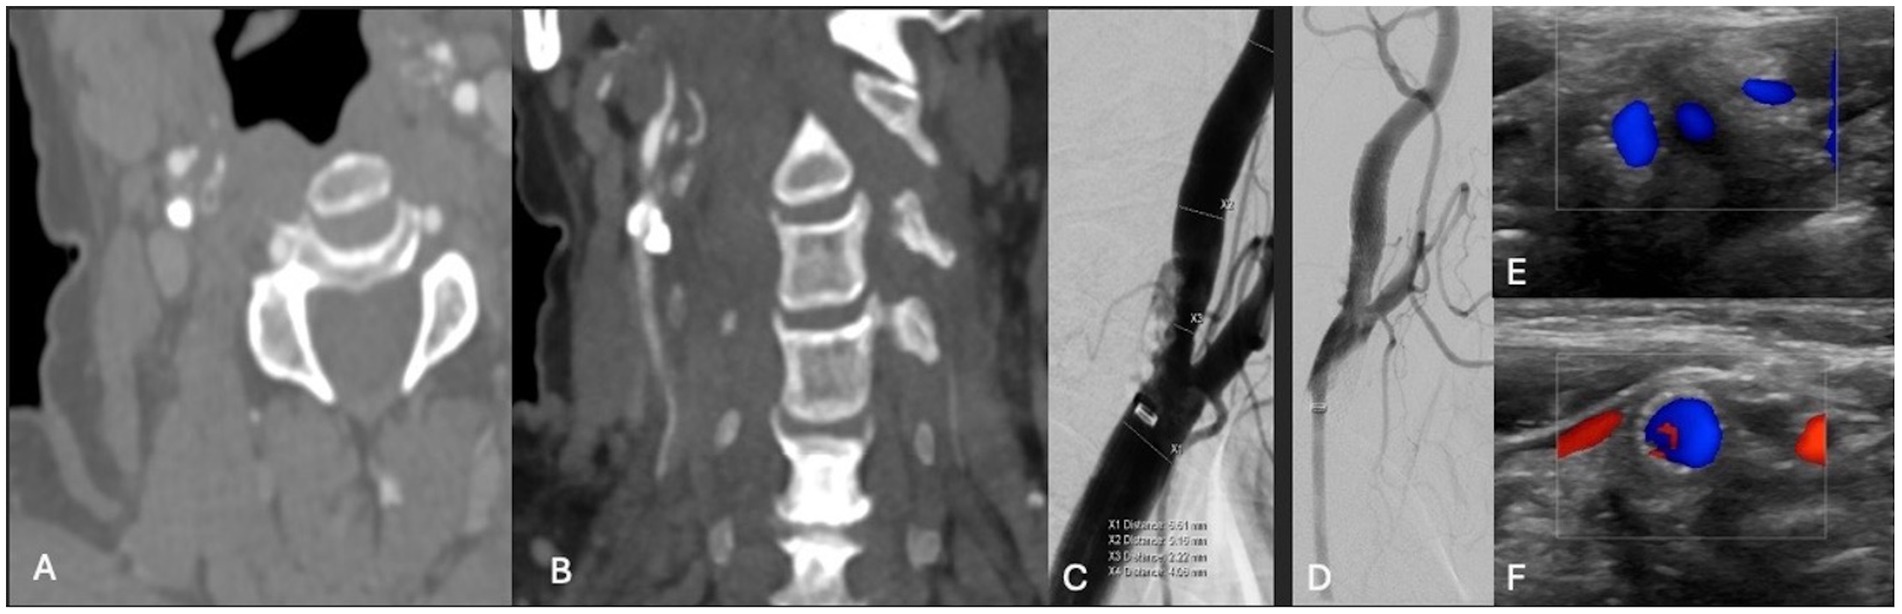

Figure 4. (A,B) Axial and coronal CTA demonstrating right ICA circumferential calcified stenosis. Catheter angiography demonstrating (C) severe R ICA stenosis. (D) Catheter angiography demonstrating improved caliber and flow following lithotripsy, stenting and angioplasty. (E,F) Duplex ultrasonography of the right carotid bulb and ICA following lithotripsy, stent and angioplasty demonstrating stent patency and normal peak systolic velocity.

A patient in their 70s presented with left-sided hemiplegia, left facial droop, and dysarthria. CTA demonstrated greater than 95% stenosis in the right ICA. Computed tomography imaging showed scattered right middle cerebral artery (MCA) infarcts (Figure 3). The patient was at high risk for surgery secondary to numerous medical comorbidities, including hypertension, peripheral vascular disease s/p peripheral bypass with subsequent thrombosis, left above-the-knee amputation, and bilateral renal stenosis. Thus, they underwent IVL and CAS with 2 episodes of sonic pulses (Figure 4). Right-sided radial access was attempted but unsuccessful in this patient; ultimately, femoral arterial access was established. Post-procedurally, the patient developed a right radial pseudoaneurysm and a hematoma at the right femoral access site, which was associated with acute blood loss anemia (hemoglobin at 6.6 g/dL) that normalized after transfusion. No surgical intervention for the femoral access site was required. Post-angiogram ultrasound findings showed PSV of 110 cm/s in the right CCA and 122 cm/s in the right ICA with a peak systolic ICA/CCA velocity ratio of 1.1 and no stenosis in the right ICA. The patient’s hospital stay was 9 days, followed by 2 weeks of inpatient acute rehabilitation. The patient did not establish neurosurgical follow-up; however, at the time of discharge from acute rehabilitation, the patient had mild weakness in the left upper extremity with improved finger dexterity and coordination.